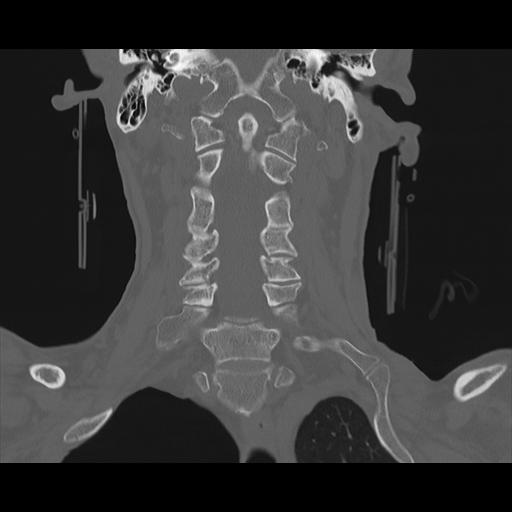

16 HUESO,,Coronal,2.000,HUESO,Coronal,